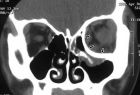

(2)CT:軸位和冠狀位和三維重建CT圖像相結合,可以明確眶緣和眶壁骨折以及軟組織損傷的具體情況,選擇手術適應徵,指導制定手術方案。